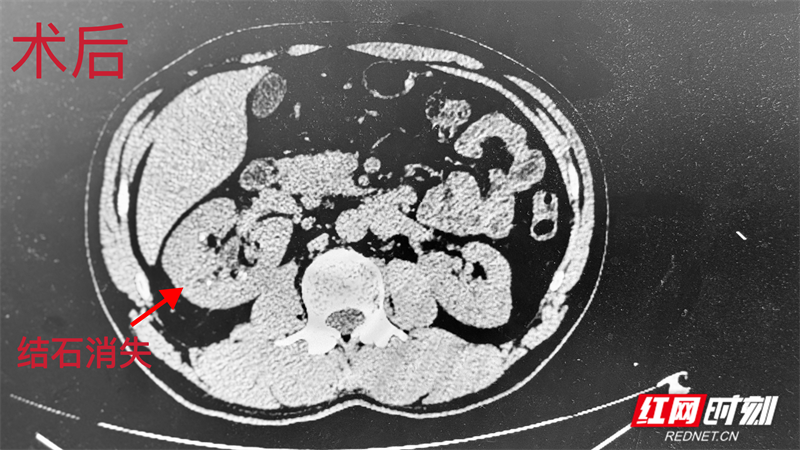

李某被肾结石困扰多年,曾多次行结石手术,但反复发作的钝痛与不适感长期困扰着他的生活和工作。经过反复咨询与比较,他最终将希望寄托在湘南地区的郴州市第四人民医院泌尿外科。面对患者的信任,泌尿外科主任陈星星接诊后,针对其肾脏内结石的位置与大小,决定采用常规开展的输尿管软镜钬激光碎石术为患者解除病痛,通过人体自然腔道精准碎石。同时,结合科室成熟的加速康复护理模式,从术前指导到术后康复,全程精准护航。

在技术与护理的双重保障下,患者从入院、手术到康复出院全程仅不到48小时,真正实现了“高、精、快”的优质诊疗体验。出院时,他欣喜地送上锦旗,由衷赞叹:“技术高、服务暖,这一趟来对了!”